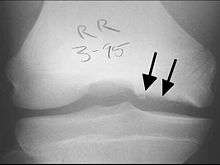

X-rays show lucency of the ossification front in juveniles. In older people, the lesion typically appears as an area of osteosclerotic bone with a radiolucent line between the osteochondral defect and the epiphysis. The visibility of the lesion depends on its location and on the amount of knee flexion used. Harding described the lateral X-ray as a method to identify the site of an OCD lesion.[35]